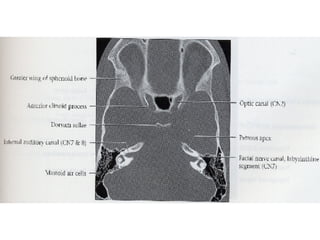

Nervos Cranianos Nervo trigêmeo- V Par 􀂄  Sensitivo 􀂄  Aferente somático geral 􀂄  Gânglio trigeminal - de Gasser 􀂄  N. oftalmico 􀂄  N. maxilar 􀂄  N. mandibular 􀂄  Exteroceptivo e Proprioceptivo

Nervos Cranianos Nervo vestíbulo-coclear- VIII Par 􀂄  Sensitivo 􀂄  Aferente somática especial 􀂄  Parte vestibular-Equilíbrio 􀂄  Parte coclear-Audição